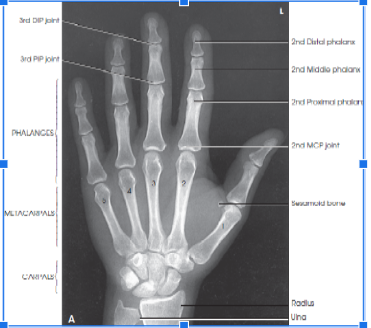

What should the part position be like for a PA hand?

Hint: think forearm and digits

A

palmar surface on IR

forearm on table

extend and separate digits to prevent soft tissue overlap

center third MCP joint to IR

Where should the central ray enter for a PA hand?

perpendicular to third MCP joint

anatomy from fingertips to distal radius and ulna

slightly separate digits with no sift tissue overlap

Evaluation criteria - What should be visible on the metacarpal and phalangeal bodies?

equal concavity of the metacarpal and phalangeal bodies

equal amount of soft tissue on both sides of the phalanges

equal distance between the metacarpal heads

evaluation criteria - what should be visible in the center of each distal phalanx?

the nail

evaluation criteria - What joint spaces should be visible in a PA hand image and what does it indicate?

MCP and IP joints. It indicates that the hand is flat on the IR